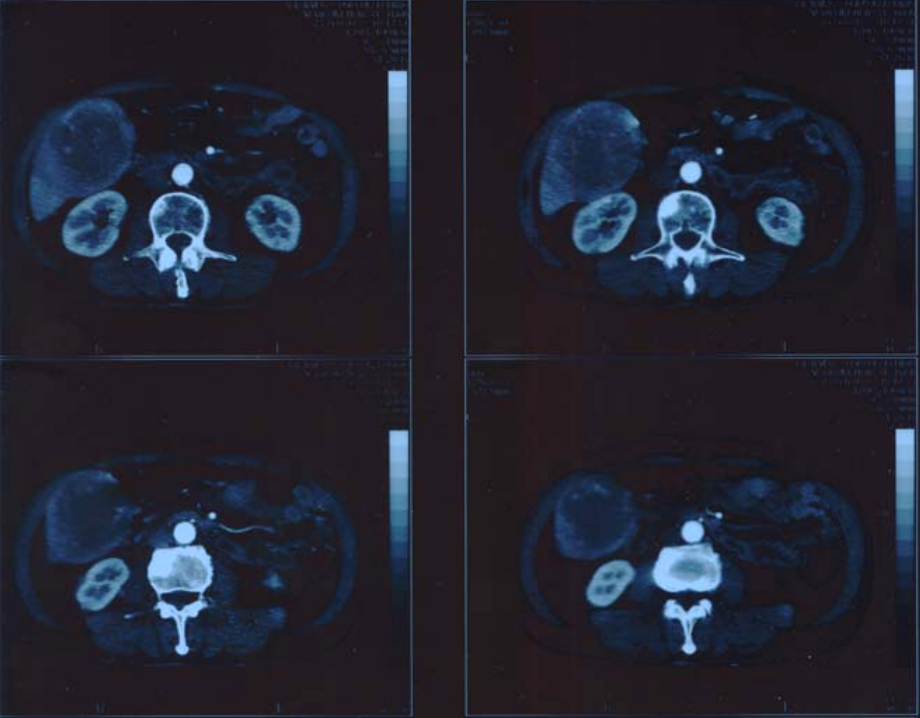

Figure4